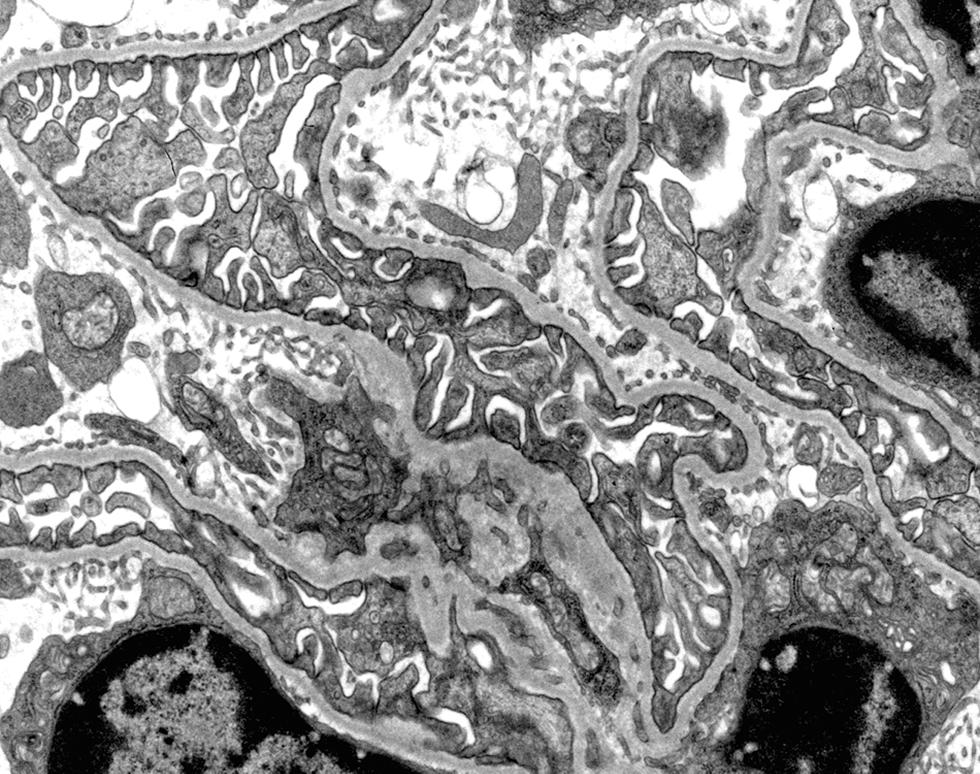

Kidney glomerulus